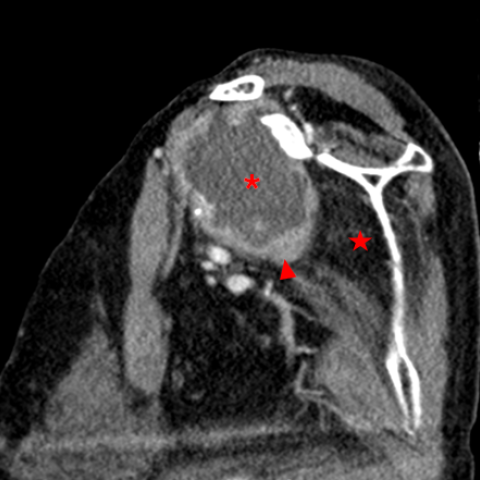

CT多平面重建软组织窗显示关节腔内存在大量积液(*),并伴有广泛的滑膜增生(箭头)。肩袖肌肉尤其是肩胛下肌明显脂肪浸润(五角星)。